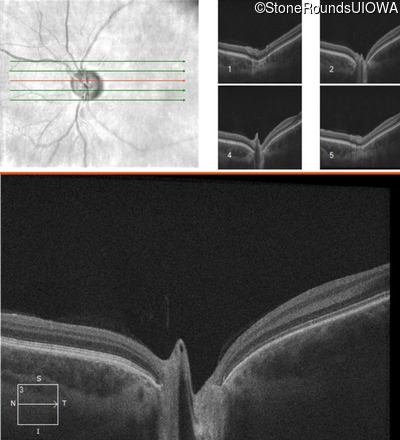

Age at visit: 17 years

This 17 year old male had normal vision until about 6 months earlier when he began to lose central vision. The left eye may have been affected prior to the right eye.

Leber Hereditary Optic Neuropathy MT-ND4 11778 A>G   MT